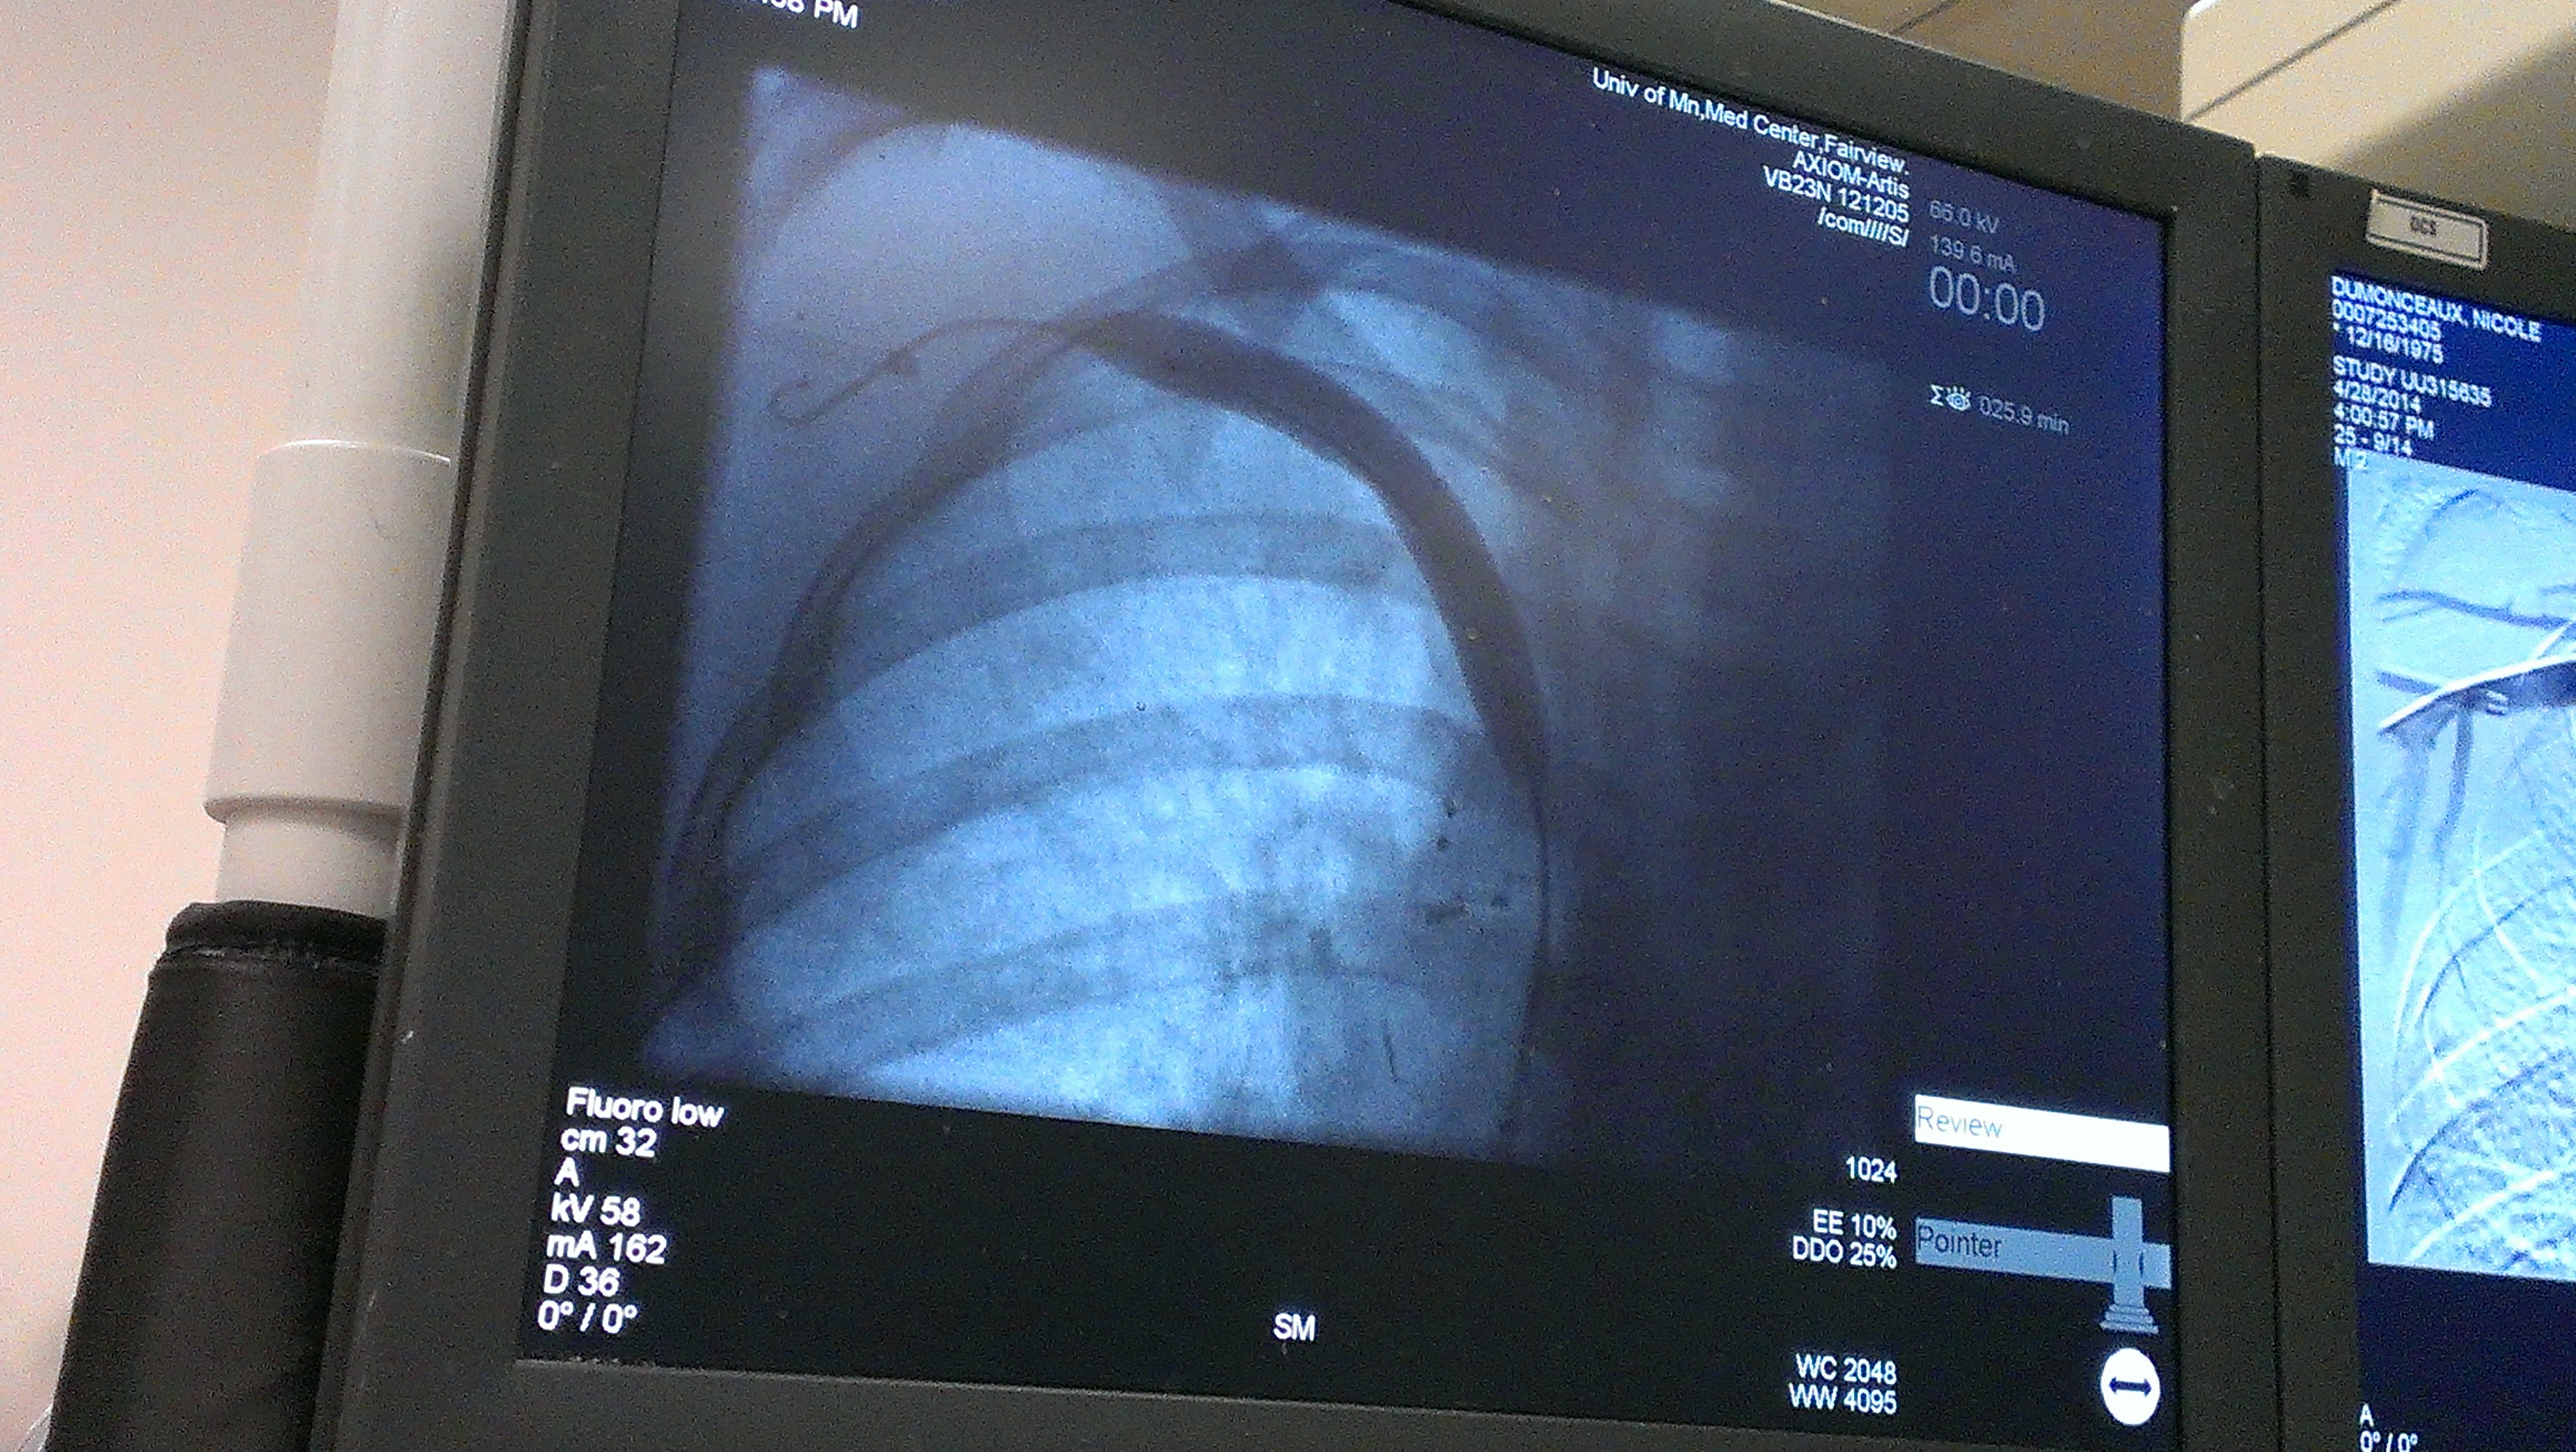

In the first picture below, blood had to travel elsewhere since the main vein was blocked. You can see all the little veins filling because of the blockage. Notice the blood flow stops where it should continue downwards. The second photo shows the flow after the angioplasty. You can see how it is one flowing movement. No more little veins. The blood is flowing as it should. I included the last picture that shows the balloon when it was inflated.